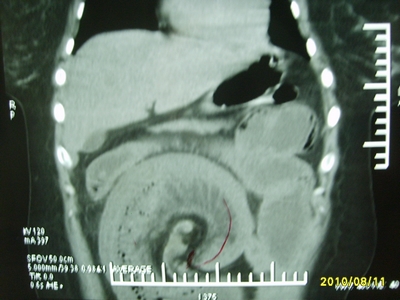

5天前突发腹痛剧烈难忍,伴解淡血水样便。近一天来腹痛缓解,没有明显的腹膜炎的体征。今天照的腹部ct。从ct上看感觉是一个绞窄性肠梗阻,但是现在没有腹痛。不好解释

请放射科的专家,帮帮看看。从影像学的角度来看看。这是不是一个绞窄性肠梗阻。

要有麻烦了,感觉小肠有套叠还有扭转改变,估计部分已有坏死。

高位肠梗阻(不全性),原因小肠(空肠)扭转,肠壁水肿增厚,成年人肠梗阻要排除合并占位,建议手术。

绞窄性肠梗阻_肠管套叠 扭转,肠壁明显水肿。

病人现在没有腹痛。怪了。从影像上来看。确实是绞窄了。但是没有腹痛。没有明显的腹膜炎的体征。确实有不好解释。难道是坏死了。反而不痛了。怪怪怪

支持绞窄性肠梗阻,肠壁明显水肿并见有多发小泡状积气--肠坏死

考虑绞窄性肠梗阻并肠坏死。